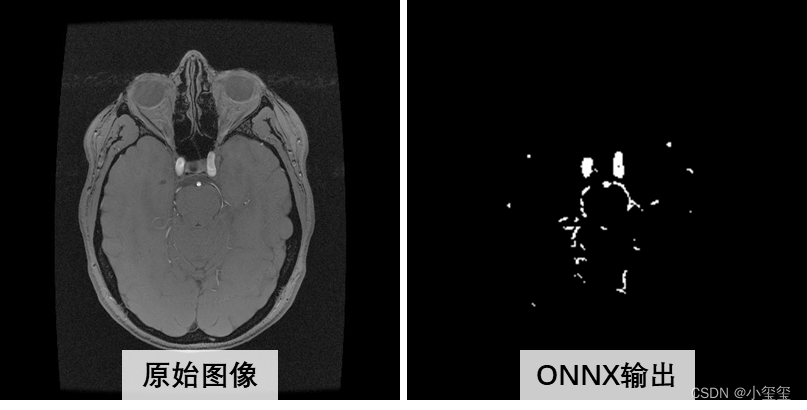

从下图可以看出,量化ONNX的推理结果和原始ONNX推理结果,主体上是相似的,局部有细微的差异(量化必然存在或多或少的精度损失,大部分情况下是可用的)。

其实我最开始以为onnx的输入preprocess_calibration,运行时候报错,错误信息说维度应该是[1,256,256,3],然后我回去看onnx结构才发现预处理节点名叫HzSQuantizedPreprocess,剩余的两个onnx节点名是HzPreprocess。